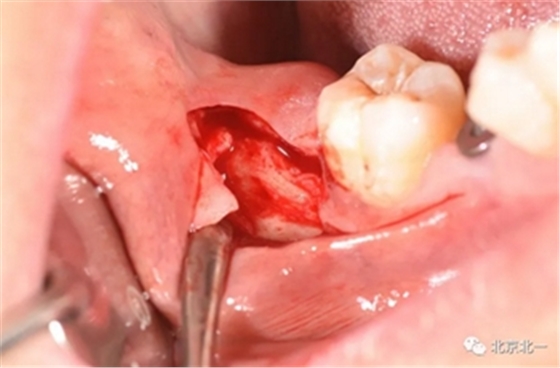

切口设计关键点偏颊侧。

去骨:原则暴露最大周径线即可, 尽可能少去骨, 微创拔除。

截冠:有丝分裂至关重要。 保证微创下拔除智齿。

术后强调冲洗创口, 搔刮血液充盈。

缝合。